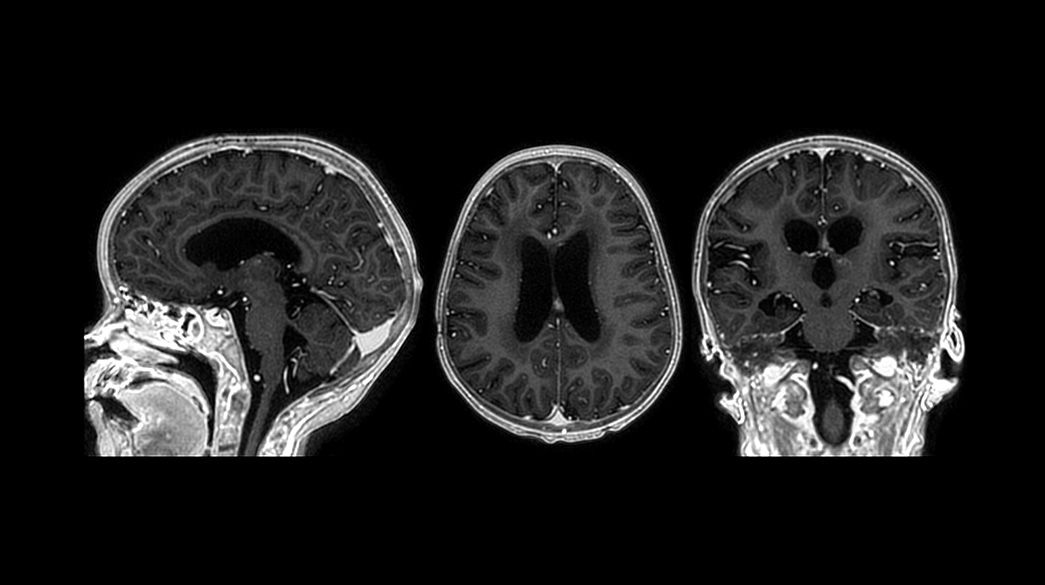

3D-Cube-3D-MP-RAGE1040-x-585

PROPELLER1040-x-585